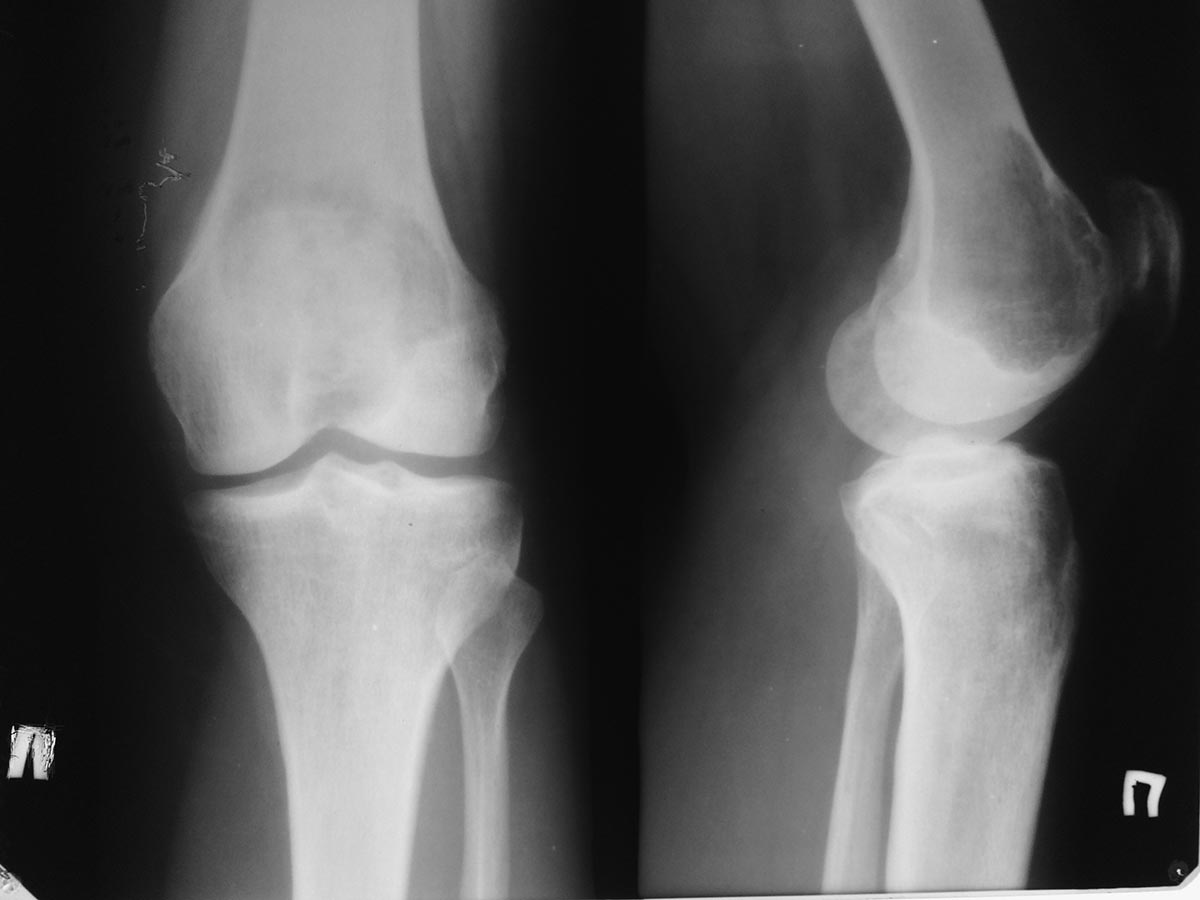

Помогите определиться с дальнейшей тактикой у молодой женщины с опухолью дистального отдела бедра. Обратилась на консультацию молодая женщина 34 лет. В январе появились боль в правом коленном суставе. Амбулаторно р- гр в прямой проекции - норма. Была незначительная травма. Боль усилилась. На днях повторно обратилась в поликлинику на рентгенограммах выявлена опухоль дистального метаэпифиза бедренгой кости. Сделано мрт. Мягкотканного компонента нет. Суставной хрящ пока интактен. Рентгенограмм прилагается. Завтра выложу мрт и сделаем ркт ( то же выложу) Предполагаю, что это остеобластокластома. Биопсию не сделаем, кт с контрастом и сцинтиграфию тоже. Учитывая угрозу патологического перелома рекомендовал костыли.

прилагаю МРТ и КТ. Образование накапливает радифармпрепарат :(

Снимки

Внешне похоже на ОБК. Другой вариант - аневризмальная киста, но вряд ли (на МРТ обычно видны множественные уровни жидкости).